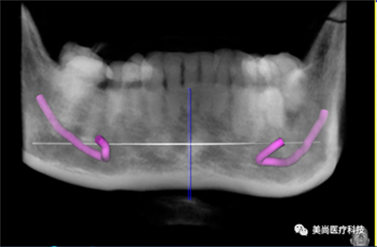

B.绘制下颌神经管

放射导板:

放射导板又称扫描义齿、放射义齿,是包涵了种植修复信息的带有放射标记点的活动义齿。它包涵了将来种植修复体的理想位置,使得医生在做术前设计时不仅考虑牙槽骨的情况,同时也考虑修复体的位置,以获得最佳的生物力学和美学效果。

安插多个放射阻射点(放射导板基托必须保证没有金属)

放射导板最终成像

为什么要用放射导板?

• 体现了以修复为向导的治疗理念

• 不仅考虑到牙槽骨骨量,还包含了软组织轮廓和牙龈厚度

• 不仅考虑种植体的理想位置,还同时兼顾修复体的位置

• 帮助医生获得最佳的生物力学和美学效果